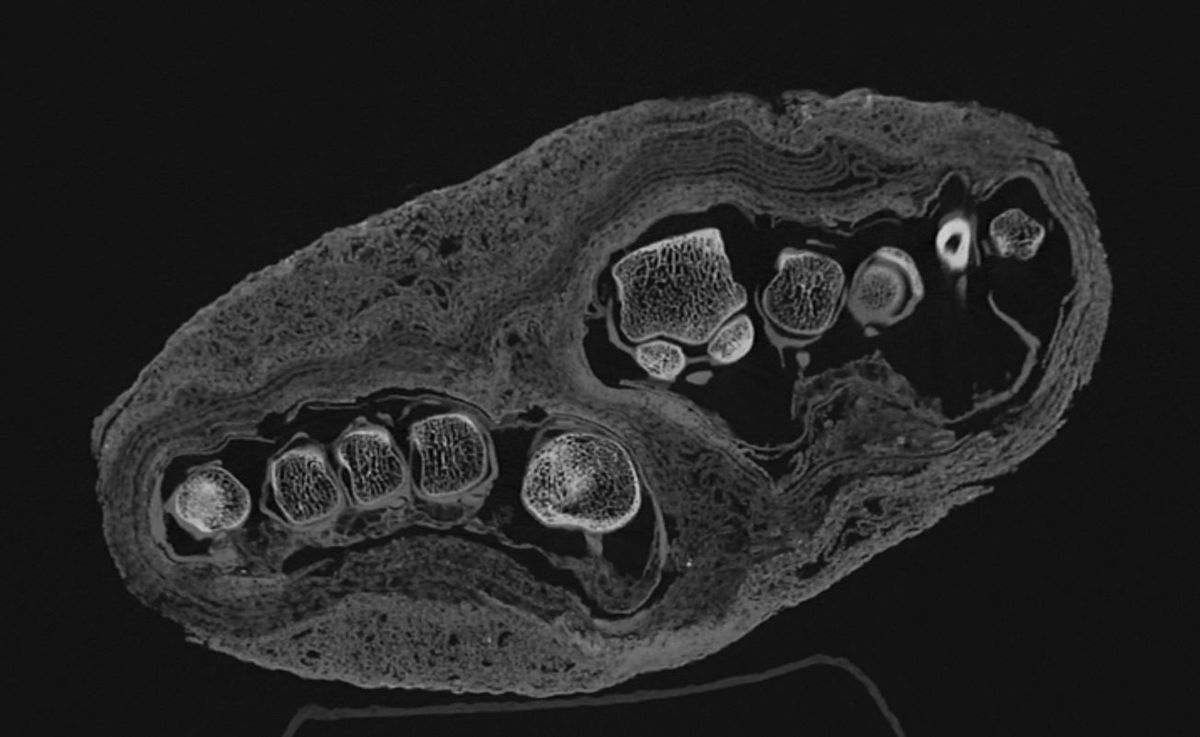

Otra parte de la investigación examinó un bulto que antes generaba dudas sobre su contenido real. Las tomografías anteriores no lograban identificar la pieza, pero la tecnología actual confirmó que se trata de un pie de un adulto. El estudio de las capas de vendajes ofrece datos sobre las técnicas de preservación utilizadas por los antiguos egipcios.

Los resultados preliminares indicaron que uno de los sujetos padecía de osteoporosis, una enfermedad que debilita los huesos. Las imágenes de alta resolución mostraron las suturas craneales y el estado de la dentadura de dos cabezas mummificadas. Esta información es vital para realizar reconstrucciones faciales en tres dimensiones durante las próximas etapas del proyecto.